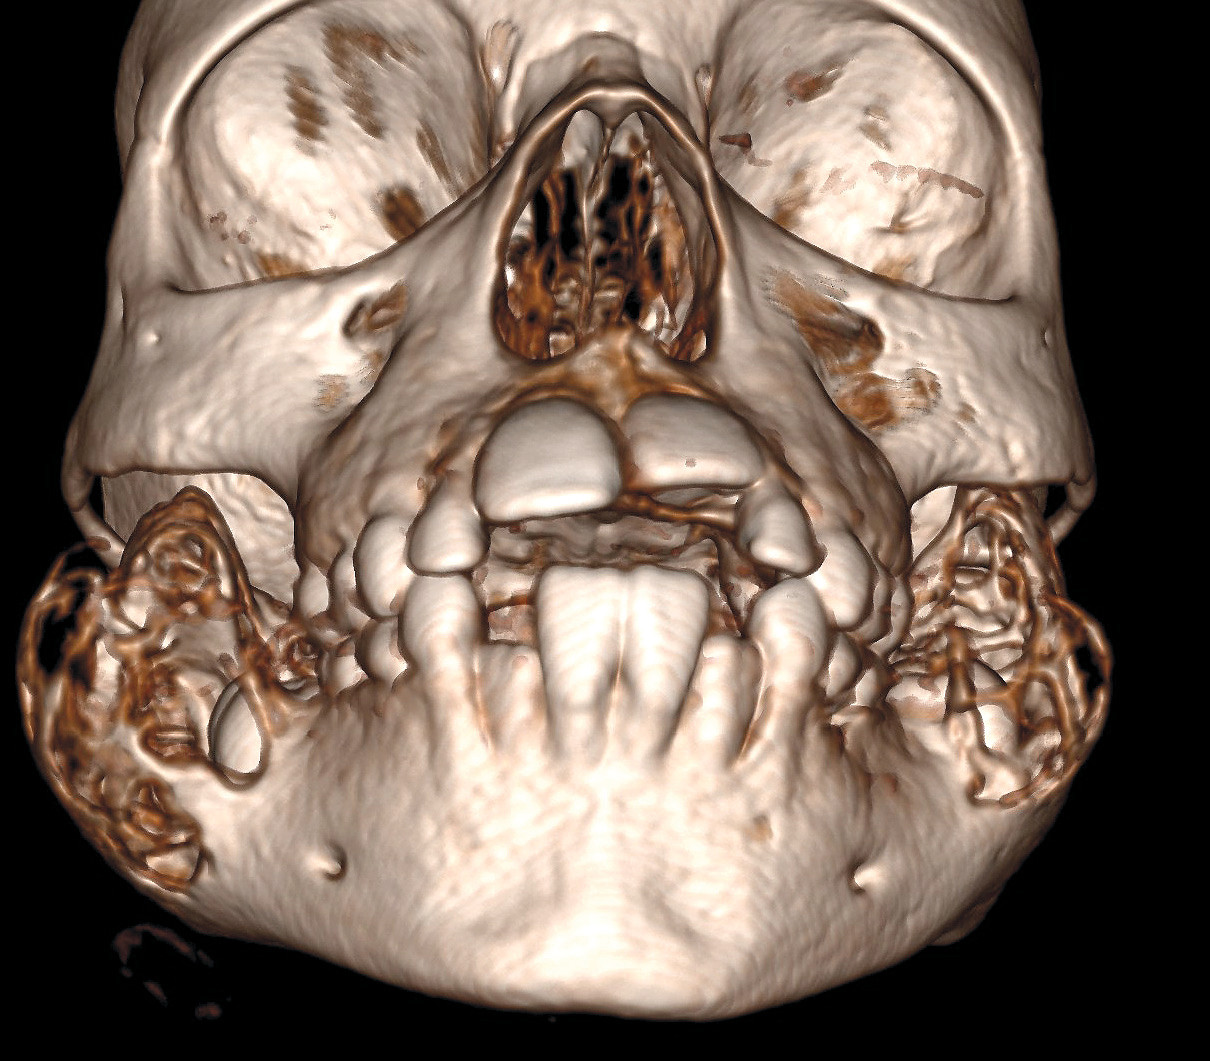

3D-CT-bildet viser ansiktsskjelettet til en tidligere frisk seksåring som ble henvist til utredning ved barneavdelingens poliklinikk på grunn av hypertrofiske kinn bilateralt. Kinnene hadde ifølge familien vært slik siden fødsel. CT av ansiktsskjelettet rekvirert på spørsmål om hypertrofi av musculus masseter avslørte symmetriske multilokulære dysplastiske ekspansjoner i ramus mandibulae på begge sider. Man fikk derfor mistanke om diagnosen kjerubisme. Fibrøs dysplasi (FD) var en aktuell differensialdiagnose, men man forventer ofte mer sklerotiske forandringer ved denne tilstanden.

Genetisk testing viste at pasienten var heterozygot for en genfeil på SH3BP2-genet som er forbundet med autosomalt dominant kjerubisme (1–3). Genet koder for et protein som fører til en kombinasjon av inflammasjon og økt produksjon av osteoklaster i kjevebeinet, som leder til den karakteristiske cystiske ekspansjonen (3, 4).

Kjerubisme er en sjelden genetisk tilstand med autosomalt dominant hereditet (2, 3). Det er publisert om lag 300 kasuistikker om tilstanden, men det mistenkes at den er underrapportert (1). Utvidelsen av kjevebeinet blir vanligvis synlig i løpet av de første leveårene og progredierer gjennom puberteten, for så å regrediere i voksen alder (1, 3). Tilstanden er benign og krever vanligvis kun konservativ behandling. Assosierte symptomer er prematur løsning av melketenner og unormal tannstilling.